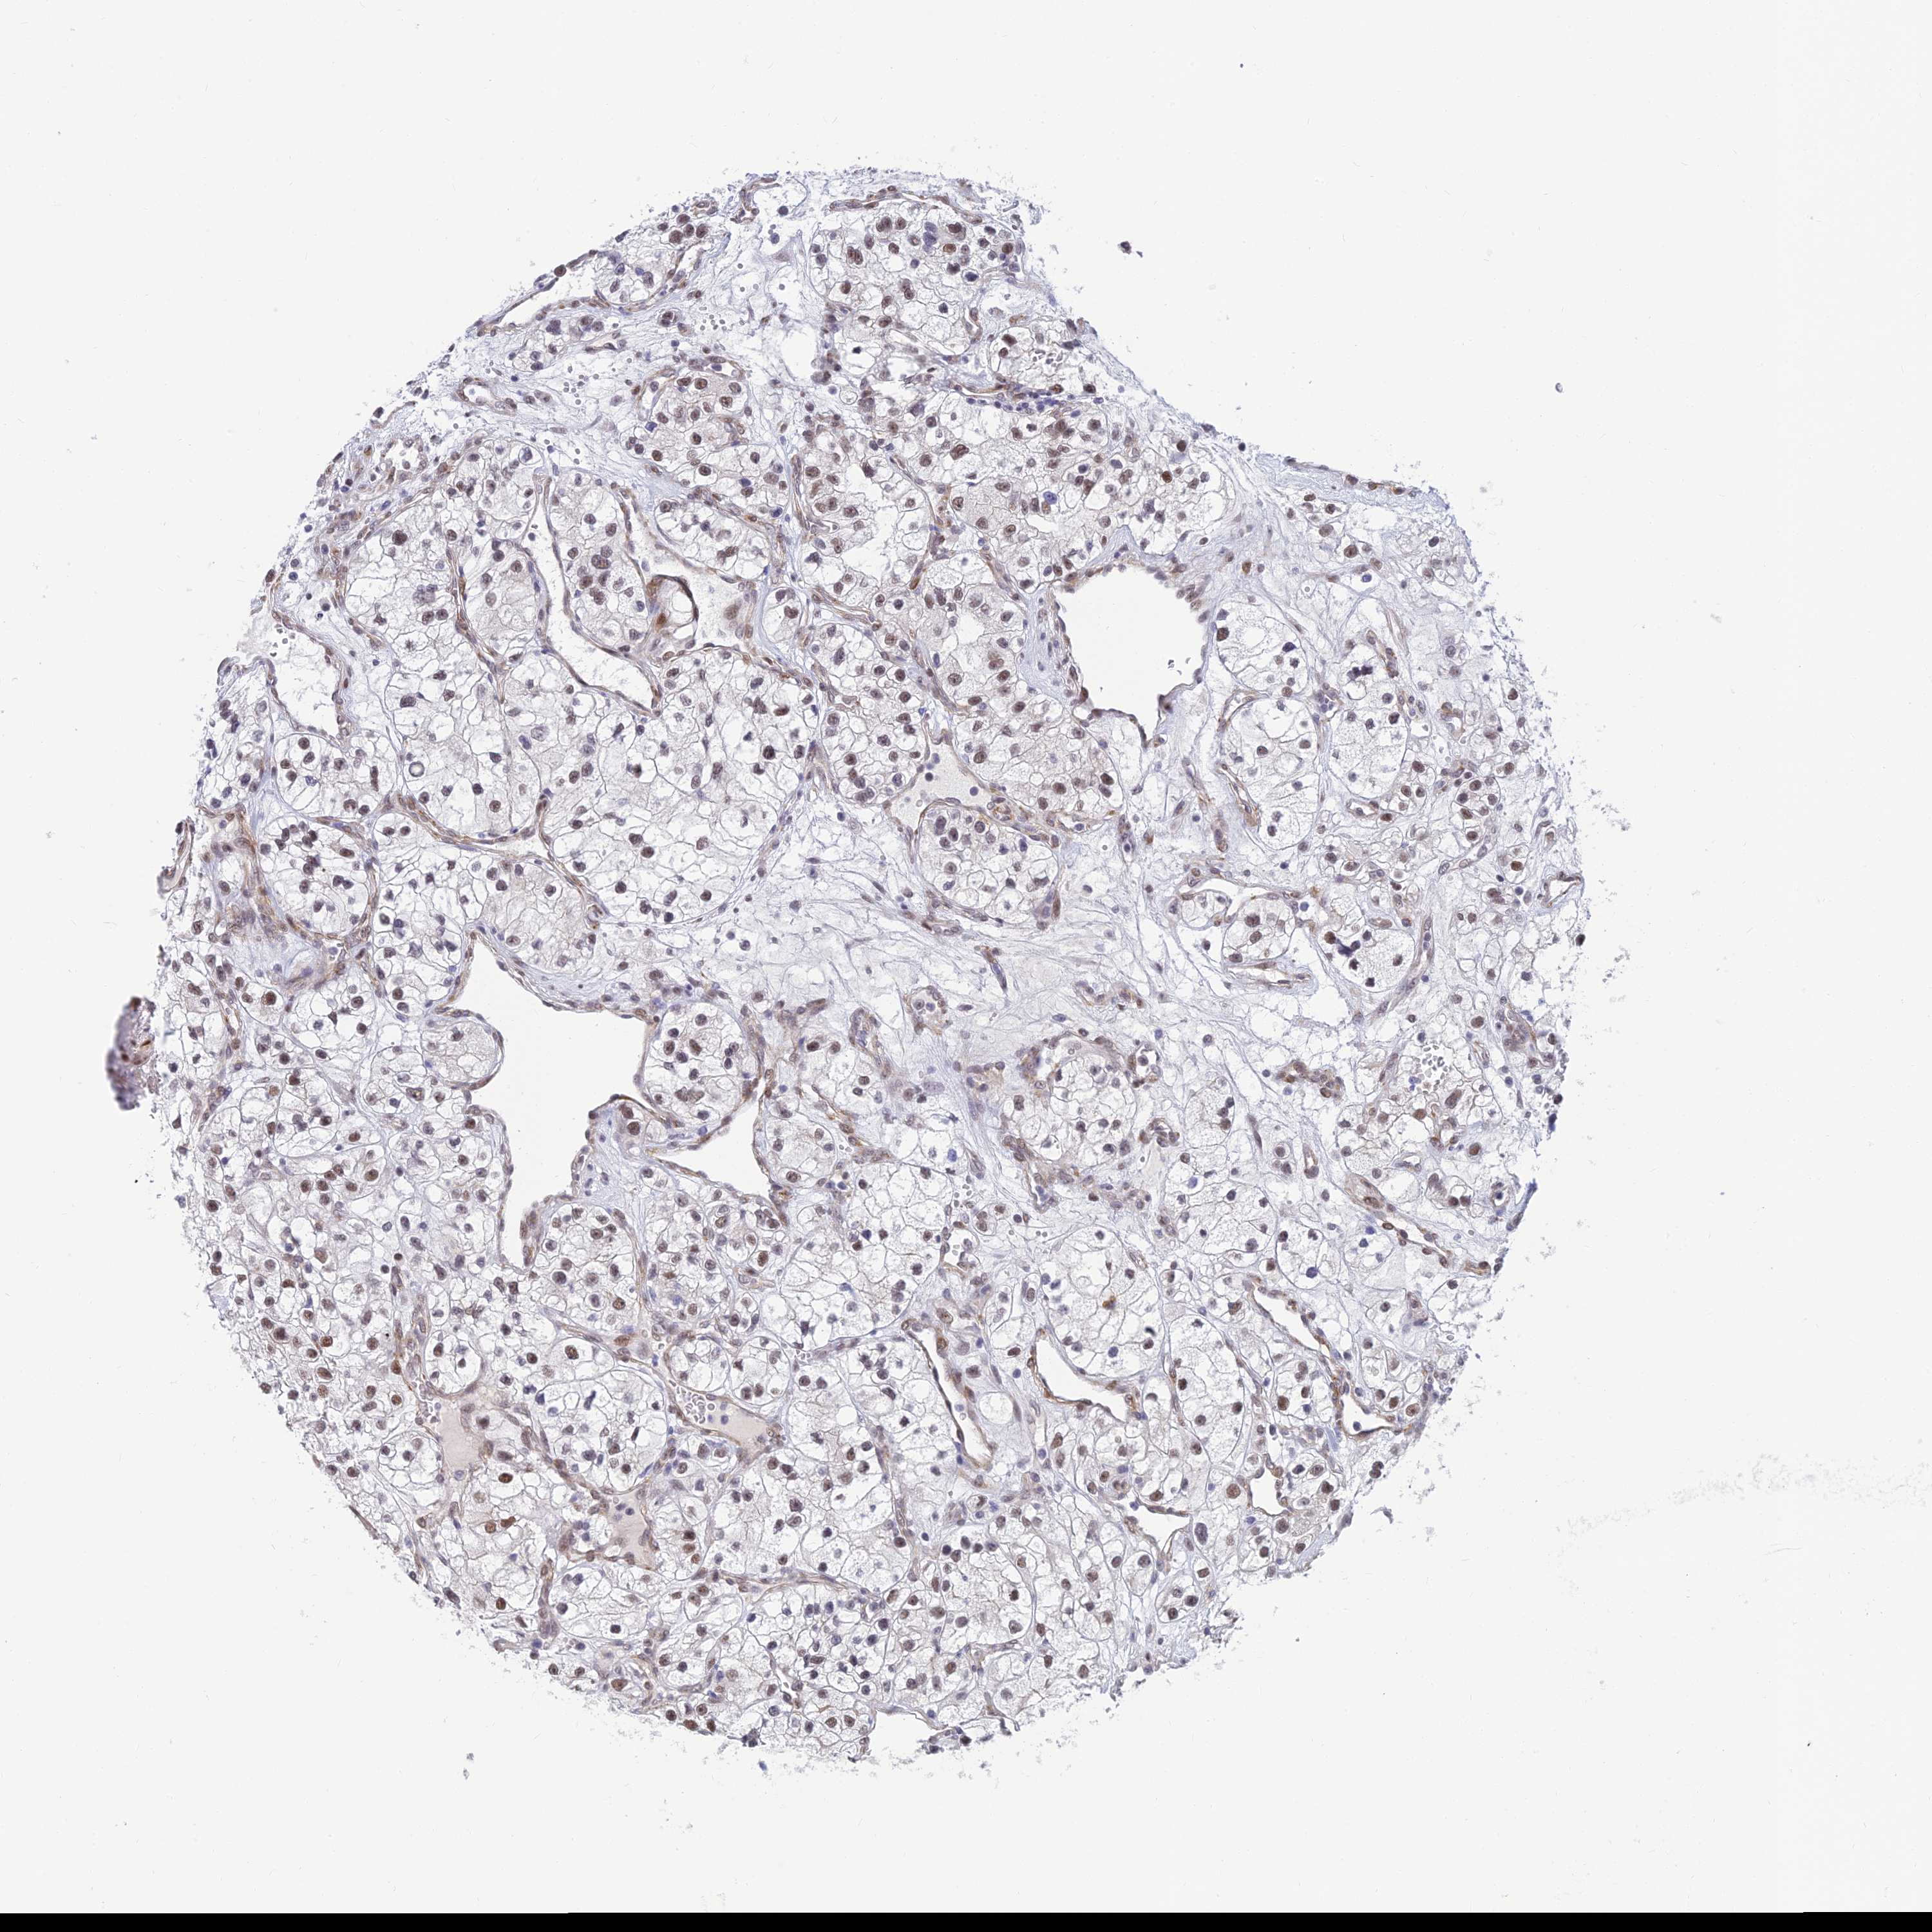

KIDNEY RENAL PAPILLARY CELL CARCINOMA (TCGA) - Interactive survival scatter ploti

The Survival Scatter plot shows the clinical status (i.e. dead or alive) for all individuals in the patient cohort, based on the same data that underlies the corresponding Kaplan-Meier plots. Patients that are alive at last time for follow-up are shown in blue and patients who have died during the study are shown in red.

The x-axis shows the expression levels (FPKM) of the investigated gene in the tumor tissue at the time of diagnosis. The y-axis shows the follow-up time after diagnosis (years). Both axes are complimented with kernel density curves demonstrating the data density over the axes. The top density plot shows the expression levels (FPKM) distribution among dead (red) and alive patients (blue). The right density plot shows the data density of the survived years of dead patients with high and low expression levels respectively, stratified using the cutoff indicated by the vertical dashed line through the Survival Scatter plot. This cutoff is automatically defined based on the FPKM cutoff that minimizes the p-score. The cutoff can be changed by dragging the vertical line or by entering a cutoff value in the square labeled "Current cut-off".

Under the Survival Scatter plot the p-score landscape (black curve; left axis) is shown together with dead median separation (red curve; right axis). Dead median separation is the difference in median mRNA expression between patients who have died with high and low expression, respectively. It is calculated as follows: median FPKM expression of dead patients with high expression - median FPKM expression of dead patients with low expression. This is intended to aid the user in visually exploring custom cutoffs and the associated p-scores and dead median separation.

Individual patient data is displayed and can be filtered by clicking on one or more of the category buttons on the top of the page. Categories describing expression level and patient information include: high, low, alive, dead, female, male and tumor stages. The scale of the x-axis can be toggled between linear and log-scale by clicking on the "x log" button. Mouse-over function shows TCGA ID, patient information and mRNA expression (FPKM) for each patient.

& Survival analysisi

Kaplan-Meier plots summarize results from analysis of correlation between mRNA expression level and patient survival. Patients were divided based on level of expression into one of the two groups "low" (under cut off) or "high" (over cut off). X-axis shows time for survival (years) and y-axis shows the probability of survival, where 1.0 corresponds to 100 percent.

CLK4 is not prognostic in Kidney Renal Papillary Cell Carcinoma (TCGA)

Best expression cut offi

Based on the FPKM value of each gene, patients were classified into two groups and association between prognosis (survival) and gene expression (FPKM) was examined. The best expression cut-off refers the FPKM value that yields maximal difference with regard to survival between the two groups at the lowest log-rank P-value. Best expression cut-off was selected based on survival analysis .

When clicking on this number, the vertical dashed line indicating cut-off, the interactive survival plot, and the Kaplan-Meier curve will be adjusted to show results based on the best expression cut-off.

: 9.01